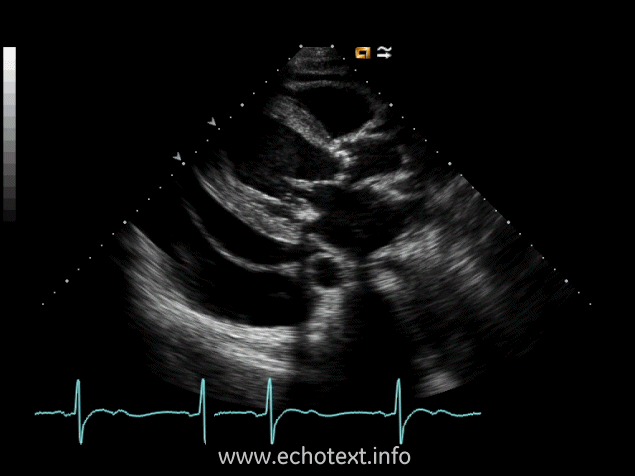

The clip below is sometimes visualized after a cardiac incident, infarction or surgery, followed by acute pericarditis. What does this image clip represent?

Dressler's syndrome

The image below is an example of what cardiac pathology:

Pericardial effusion

Constrictive pericarditis with pericardial effusion